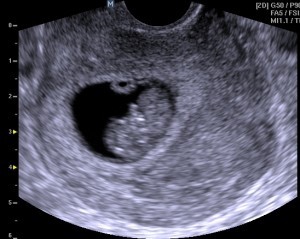

8-я неделя

Календарь беременностиЗаканчивается второй месяц беременности, который считается одним из самых сложных периодов беременности женщины. В этот период следует быть особенно осторожной и аккуратной.

Можно смело заявить: теперь в животе у вас не эмбрион, а плод, маленький младенец. Он уже не похож на зародыша млекопитающих, а выглядит как маленький человечек.

Длина малыша от макушки до копчика составляет - 1,4-2 см. Вес - 3-13 г.